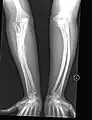

Having the same clinical features as Type IV, it is distinguished histologically by "mesh-like" bone appearance. Further characterized by the "V triad" consisting of (a) radio-opaque band adjacent to growth plates, (b) hypertrophic calluses at fracture sites, and (c) calcification of the radio-ulnar interosseous membrane.[24]

OI Type V leads to calcification of the membrane between the two forearm bones, making it difficult to turn the wrist. Another symptom is abnormally large amounts of repair tissue (hyperplasic callus) at the site of fractures. Other features of this condition include radial head dislocation, long bone bowing, and mixed hearing loss.

OI Type V in a child